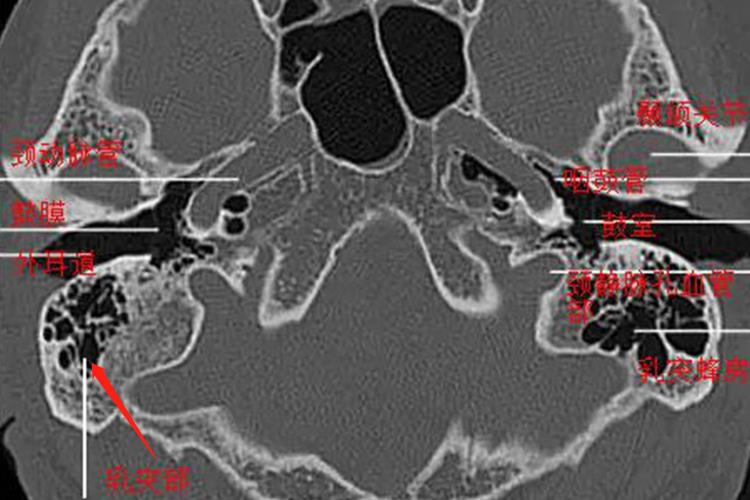

乳突又称乳突部,位于鳞部的后下方,呈锥形突起,上方与鳞部以线为界,前下与鼓部融合形成鼓乳裂,可分为内、外两面及上、后两缘。其外侧面粗糙,在外侧面道上棘后方,外耳道后壁向上延伸与颞线相交所成之三角形区域,称为道上三角区。后缘处的乳突孔,贯穿骨内外,有乳突导血管通过此孔,使颅外静脉与乙状窦沟通。